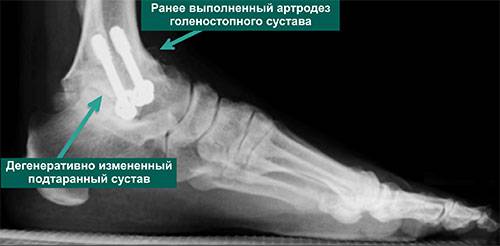

- 2 стадия. Боль выражена сильнее, проявляется чаще, даже во время отдыха. Отмечаются мозоли, покраснения, отечность, местное увеличение температуры тела. Снижается активность стоп, постепенно развивается атрофия мышц. На рентгеновских снимках (фото представлены ниже) четко видно деформированную костную ткань и остеофиты.

Стоить заметить, что признаки артроза ярко выражены только на последних стадиях. Выявить в начале формирования болезнь можно только с помощью рентгена. Поначалу визуальные изменения в этой области тела не проявляются. Однако стоит отметить, что эта болезнь способна усложнить жизнь человека.

Для диагностики заболевания пациентам назначают рентгенографию. На снимках можно увидеть патологические изменения, которыми сопровождается артоз пятки. К тому же результаты обследования помогают определить стадию развития болезни.